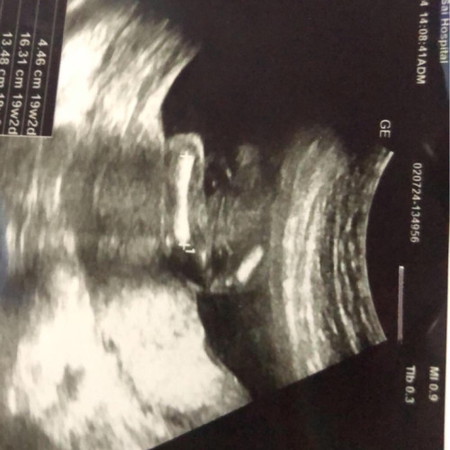

แม่ช่วยทายเพศให้หน่อยค่ะ

19วีคไปซาวมาหมอมองไม่เห็นเลยค่ะลุ้นมากอยากรู้เพศแล้ว

น้องเป็นผู้หญิงค่ะมีกลีบ

ญ.ค่ะ